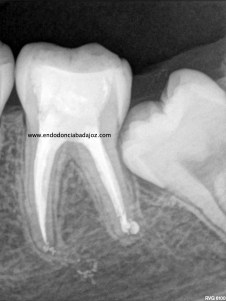

Como todos sabemos, encontrarnos dos conductos en la raíz mesiovestibular de un primer molar superior, cada vez es más frecuente, no por que antes no existiesen, sino por que cada vez somos más conscientes de su existencia,de la anatomía del sistema de conductos tan complicada que puede alojarse en esta raíz, con lo que buscamos ese cuarto conducto. Partamos de la base , que si los buscamos podremos localizarlos, pero hay veces que la cosa se pone algo más complicado, cuando, podemos apreciar un conducto más, quizás se trate de un istmo prolongado del cuarto conducto, pero que en cualquier caso debemos desbridar , limpiar y obturar, con lo que debemos tratarlo como otro conducto.

(un molar superior con tres conductos mesiales)